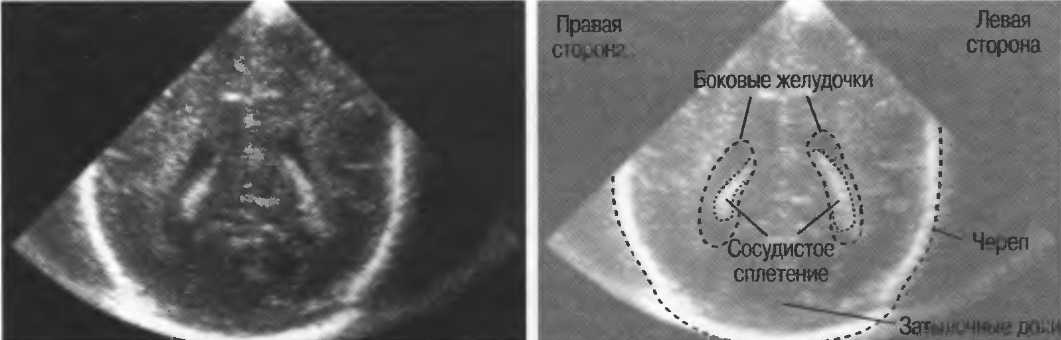

3. Ультразвуковые исследования в педиатрии. Для детей необходим датчик с частотой 5 МГц с глубиной фокусировки на 5-7 см. При исследовании мозга новорожденного используется секторный датчик с частотой 7,5 МГц с глубиной фокусировки на 4-5 см (этот датчик также используется для исследования яичек и структур шеи у взрослых).